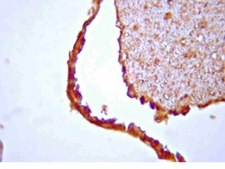

Non-Lot Specific Tested Application 1:

Immunohistochemistry: Working dilutions of 1:50-1:500 in rat brain and spinal cord (paraffin embedded)